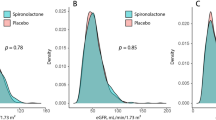

At baseline, the participants’ average age was 60.51 ± 10.03 years, with 6,300 (79.08%) males. The average systolic blood pressure (SBP) and HbA1c were 147.27 ± 20.58 mmHg and 7.57 ± 1.66%, respectively. The eGFRcys, eGFRcr, and eGFRdiff were 88.77 ± 22.73 mL/min*1.73 m2, 93.41 ± 15.43 mL/min*1.73 m2, and − 4.59 ± 18.72 mL/min*1.73 m2, respectively. The eGFR evaluated by serum creatinine and cystatin C showed inconsistent results, with eGFRcys values generally being lower than eGFRcr.

More than half of participants had a baseline eGFRdiff between − 15 and 15 mL/min/1.73 m2 (4679 participants [58.7%]; midrange eGFRdiff); 2280 participants (28.6%) had an eGFRdiff less than − 15 mL/min/1.73 m2 (negative eGFRdiff ), and 1008 participants (12.6%) had an eGFRdiff of 15 mL/min/1.73 m2 or greater (positive eGFRdiff). Compared with the other 2 eGFRdiff groups, participants in the negative eGFRdiff group were older, more often female, with higher baseline SBP, BMI, uACR and more anti-diabetic and antihypertensive treatment (Table 1; Fig. 1).